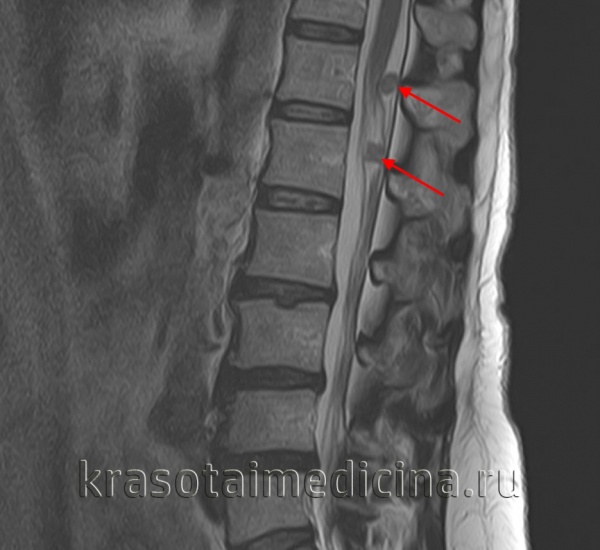

3. МРТ при шванноме яремного отверстия:

• Т1 ВИ:

о Трубчатое или гантелеобразное объемное образование ЯО

о Как правило, изоинтенсивно по сравнению с головным мозгом

о Характерно смещение внутренней сонной артерии в носоглоточной части каротидного пространства переднемедиальной поверхностью ШЯО

о В ткани даже крупных опухолей не возникает «пустот потока» («перец») или гиперинтенсивных очагов-скоплений продуктов распада крови («соль»)

• Т2ВИ:

о Интенсивный сигнал по сравнению с белым веществом о В ткани крупных ШЯО отмечается усиление сигнала кистозных зон:

- В 25% ШЯО выявляются интрамуральные кисты